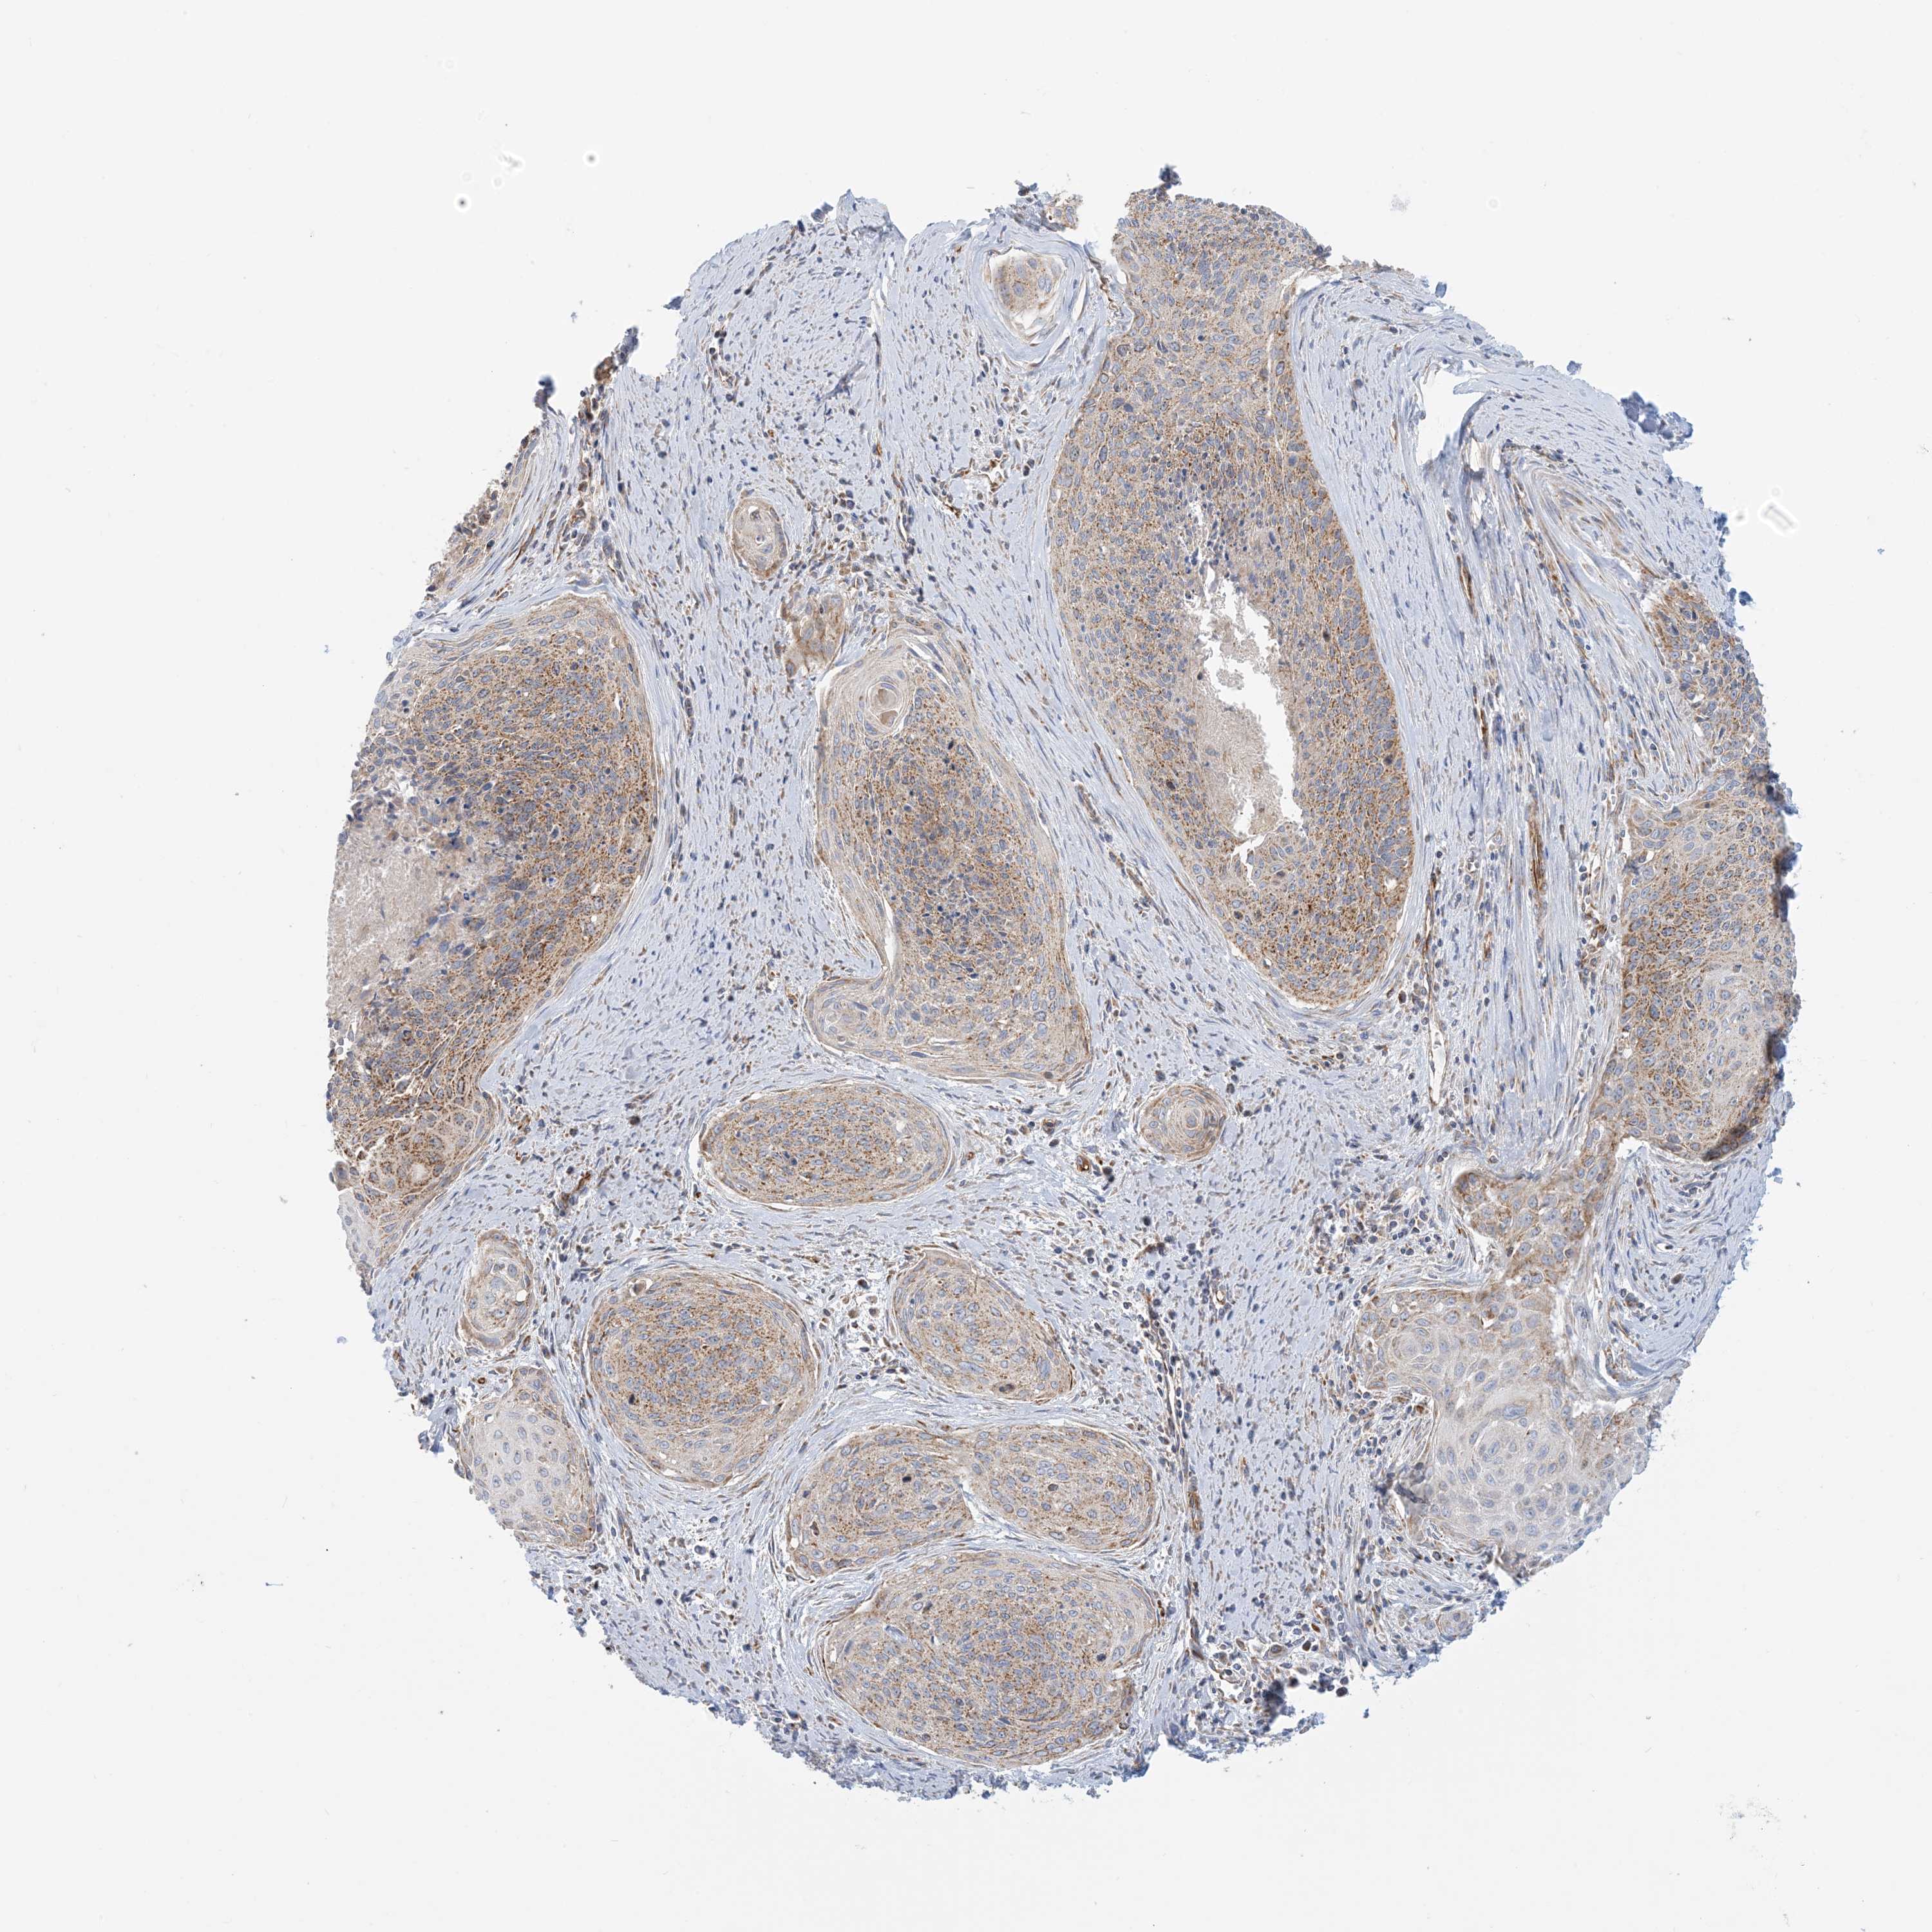

CERVICAL CANCER - Protein expressioni

A mouse-over function shows sample information and annotation data. Click on an image to view it in a full screen mode. Samples can be filtered based on level of antibody staining by selecting one or several of the following categories: high, medium, low and not detected. The assay and annotation is described here.

Note that samples used for immunohistochemistry by the Human Protein Atlas do not correspond to samples in the TCGA dataset.

Antibody stainingi

Antibody staining in the annotated cell types in the current human tissue is reported as not detected, low, medium, or high, based on conventional immunohistochemistry profiling in selected tissues. This score is based on the combination of the staining intensity and fraction of stained cells.

Each image is clickable and will lead to virtual microscopy that enables deeper exploration of all samples and also displays staining intensity scores, fraction scores and subcellular localization as well as patient and tissue information for each sample.

Antibody HPA031966

Staining

High

Medium

Low

Not detected

Intensity

Strong

Moderate

Weak

Negative

Quantity

>75%

75%-25%

<25%

None

Location

Nuclear

Cytoplasmic/membranous

Cytoplasmic/membranous,nuclear

Squamous cell carcinoma, NOS

Adenocarcinoma, NOS